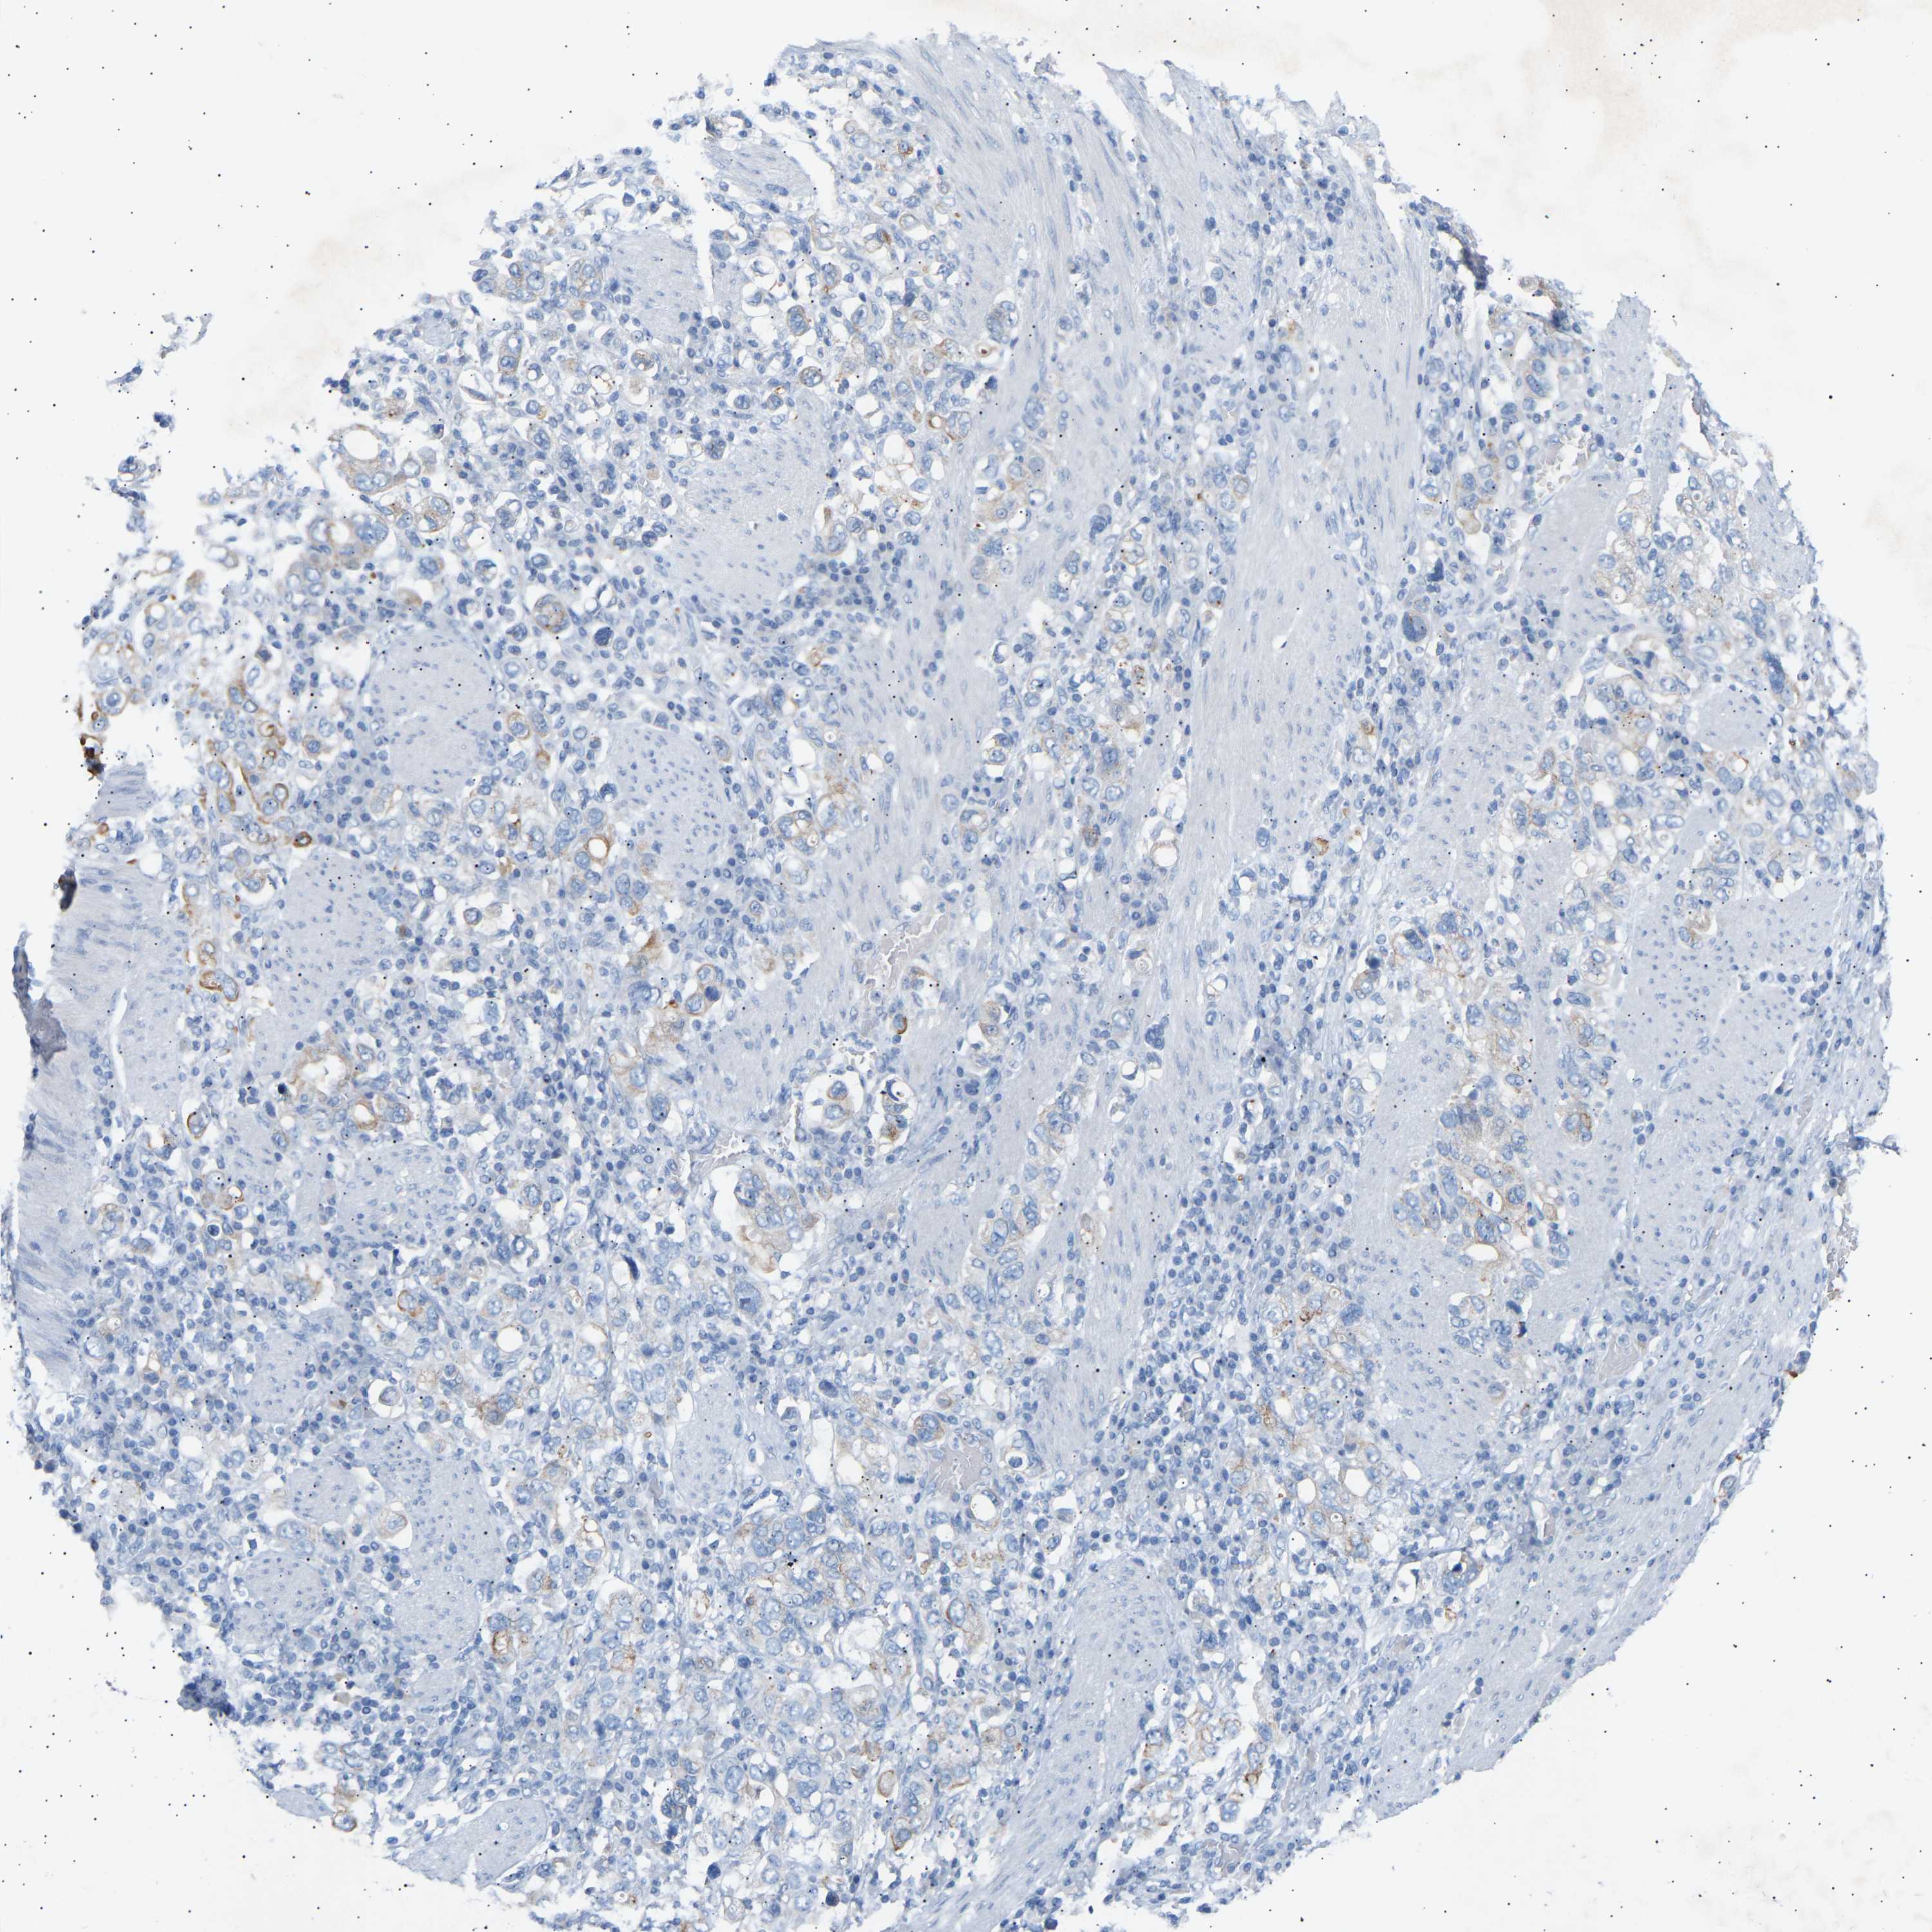

STOMACH CANCER - Protein expressioni

A mouse-over function shows sample information and annotation data. Click on an image to view it in a full screen mode. Samples can be filtered based on level of antibody staining by selecting one or several of the following categories: high, medium, low and not detected. The assay and annotation is described here.

Antibody stainingi

Antibody staining in the annotated cell types in the current human tissue is reported as not detected, low, medium, or high, based on conventional immunohistochemistry profiling in selected tissues. This score is based on the combination of the staining intensity and fraction of stained cells.

Each image is clickable and will lead to virtual microscopy that enables deeper exploration of all samples and also displays staining intensity scores, fraction scores and subcellular localization as well as patient and tissue information for each sample.

Antibody HPA020235

Staining

High

Medium

Low

Not detected

Intensity

Strong

Moderate

Weak

Negative

Quantity

>75%

75%-25%

<25%

None

Location

Nuclear

Cytoplasmic/membranous

Cytoplasmic/membranous,nuclear

Adenocarcinoma, NOS